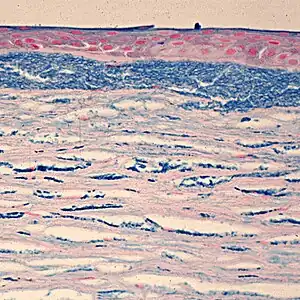

| Colloidal iron staining shows deposition of glycosaminoglycans in the cornea | |

Macular Corneal Dystrophy is an autosomal recessive genetic disorder caused by mutations in the carbohydrate sulfotransferase gene (CHST6), resulting in abnormal proteoglycan synthesis. The accumulation of abnormal glycosaminogycans in the corneal epithelium and stroma leads to progressive opacification of the cornea and subsequent loss of visual acuity.[7][8] There are three variants of MCD characterized by immunophenotype:

Histopathological staining shows characteristic alcian blue-positive deposits.[7] Various imaging modalities, including confocal microscopy and ocular coherence tomography, can provide information about the changes within the cornea and may be suitable replacements for tissue biopsy and excision.[8]